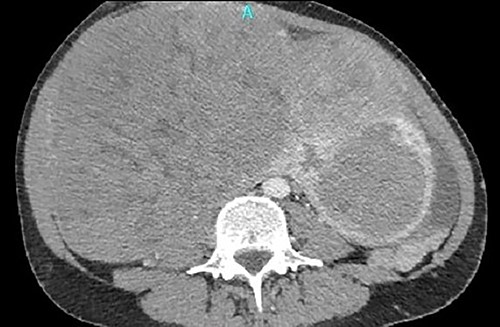

One month later, after vascular consultation, a chest and pelvis computed tomography angiography was performed and a huge mass originating from the uterine wall was revealed (26 cm in diameter) (Fig. 1). The mass compressed the surrounding organs, especially IVC (Fig. 2). Furthermore, thrombosis of left femoral and external and common iliac veins, as well as infrarenal IVC patency (without clarification of IVC thrombosis), was detected. The common, internal and external right iliac veins were patent, and no PE was detected.

A huge mass originating from the uterine wall was revealed after pelvis CTA.